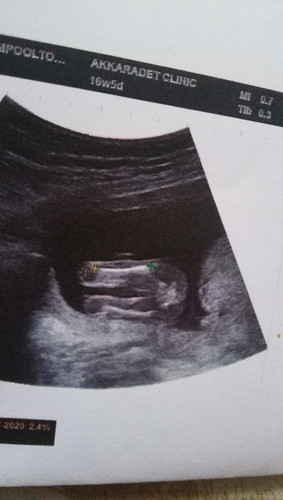

ไปซาวมาเมื่อวานค่ะ อยากรู้ว่าลูกเพศอะไร ใครรู้ช่วยบอกหน่อยค่ะ ?❣️

ลูกสาวมั้ยค่ะ หมอว่าไงบ้างค่ะแม่

น่าจะเป็นผู้หญิงค่ะ